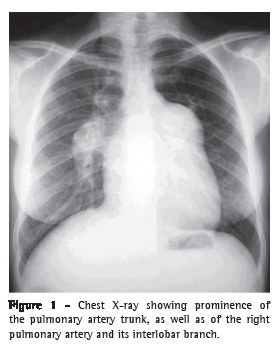

An ultrasound scan of the abdomen revealed moderate central and peripheral echogenic periportal thickening, gallbladder wall thickening, with signs of portal hypertension (portal vein = 13 mm and splenic vein = 10 mm), and an 11-mm paraumbilical vein as a pathway of collateral circulation, all of which are consistent with hepatosplenic schistosomiasis. The longitudinal diameter of the spleen was 117 mm. At the first assessment, upper digestive tract endoscopy revealed small-diameter esophageal varices. The serology was negative for hepatitis B surface antigen (HBsAg), antibody to hepatitis B surface antigen (anti-HBs), antibody to hepatitis B core antigen (anti-HBc), and antibody to hepatitis C virus (anti-HCV). A chest X-ray showed dilated pulmonary arteries and right heart enlargement (Figure 1), both of which were confirmed by chest CT (Figure 2). An electrocardiogram showed signs of right heart overload. An echocardiogram revealed right atrial and right ventricular enlargement, with an estimated pulmonary artery systolic pressure of 145 mmHg, as well as aneurysmal dilatation of the pulmonary artery (56 mm). The spirometry results were as follows: FEV1 = 2.22 L (76%); FVC = 3.04 L (90%); FEV1/FVC = 73.03%; and a negative bronchodilator test. The 6MWD was 153.6 m, and the test was interrupted, due to presyncope, at 75 s. Angiotomography and lung scintigraphy, which had been performed previously, revealed aneurysmal dilatation of the pulmonary artery, no pulmonary artery filling defects, and a low probability of pulmonary embolism. Right heart catheterization showed a pulmonary artery systolic pressure of 140 mmHg, a mean pulmonary artery pressure of 88 mmHg, a cardiac index of 3.0 L  min−1  m−2, and pulmonary vascular resistance of 23.0 Woods. Pulmonary vasoreactivity testing with nitric oxide was negative.

Data from facilities specializing in the treatment of patients with PH in Brazil suggest that schistosomiasis is the cause of the disease in at least 30% of such patients.(16) The clinical presentation seems to be similar to that of idiopathic PAH, being characterized by dyspnea on exertion, weakness, cough, palpitation, chest pain, and hemoptysis.(16) Chest X-ray usually shows dilatation of the pulmonary artery trunk and cardiomegaly due to right ventricular enlargement.(17,18)